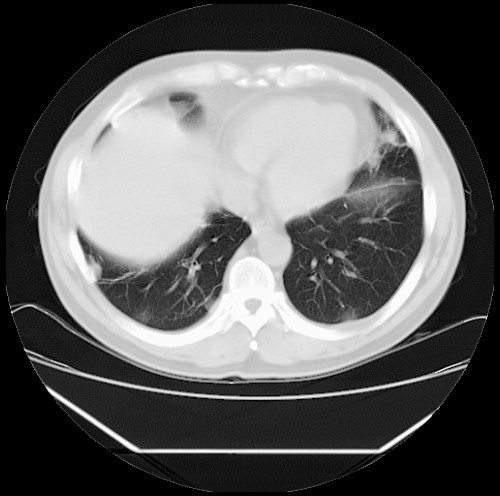

标题: CT22085:双肺多发结节

男,44岁,咳嗽,痰中带血2天。

病灶大部分位于胸膜下,结节大小相差不是很大,肺尖太干净。这种结核没见过,我认为可排除。

首先考虑转移,不除外肉芽肿、真菌感染。建议查其它。

除肺内及胸膜下可见多发大结节外,在肺小叶中心核、小叶间隔及支气管血管束上亦可见多方小结节,可以认为是随机分布。考虑转移可能性大。

仔细观察病灶形态,病灶边界部分清楚,结合临床症状,首先考虑转移,纵隔内多个肿大淋巴结影。

双肺血管纹理末端多发类圆形结节,边界光滑清晰 气管前腔静脉后淋巴结肿大

考虑转移瘤

沿血管分布,位于血管末端。转移瘤多见,血行性菌栓也可见到。

本例双肺多发类圆形高密度灶,边清,结合病史多考虑双肺多发转移改变,可以结合实验室检查。